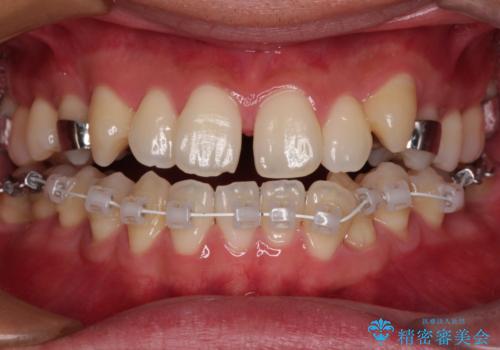

- 矯正装置

- 審美装置

- 上下前歯部のデコボコを主訴として来院された患者様です。

上顎の歯列弓が下顎に対して狭いため、臼歯のかみ合わせがが咬頭対咬頭の状態です。

上顎の急速拡大装置を使用して、上顎骨を側方に拡大することで上顎歯列弓を拡大し、それに伴い下顎歯列弓も拡大できるようにして、歯列を整えていくこととしました。